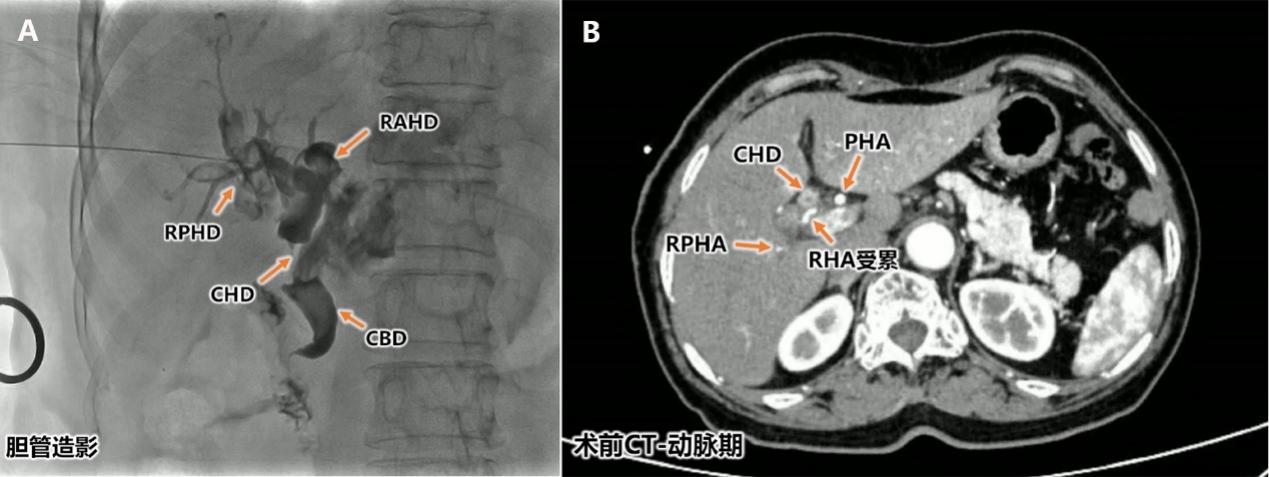

本例患者在接受胆囊切除术后一月余,出现皮肤巩膜黄染,经检查诊断考虑胆囊癌累及胆囊管及肝门胆管(图 2A),肿瘤已累及肝门区胆管并侵犯了右肝动脉主干及其分支起始部(图 2B)。这种情况下的根治性手术极具挑战,如同在「生命禁区」进行精细作业。